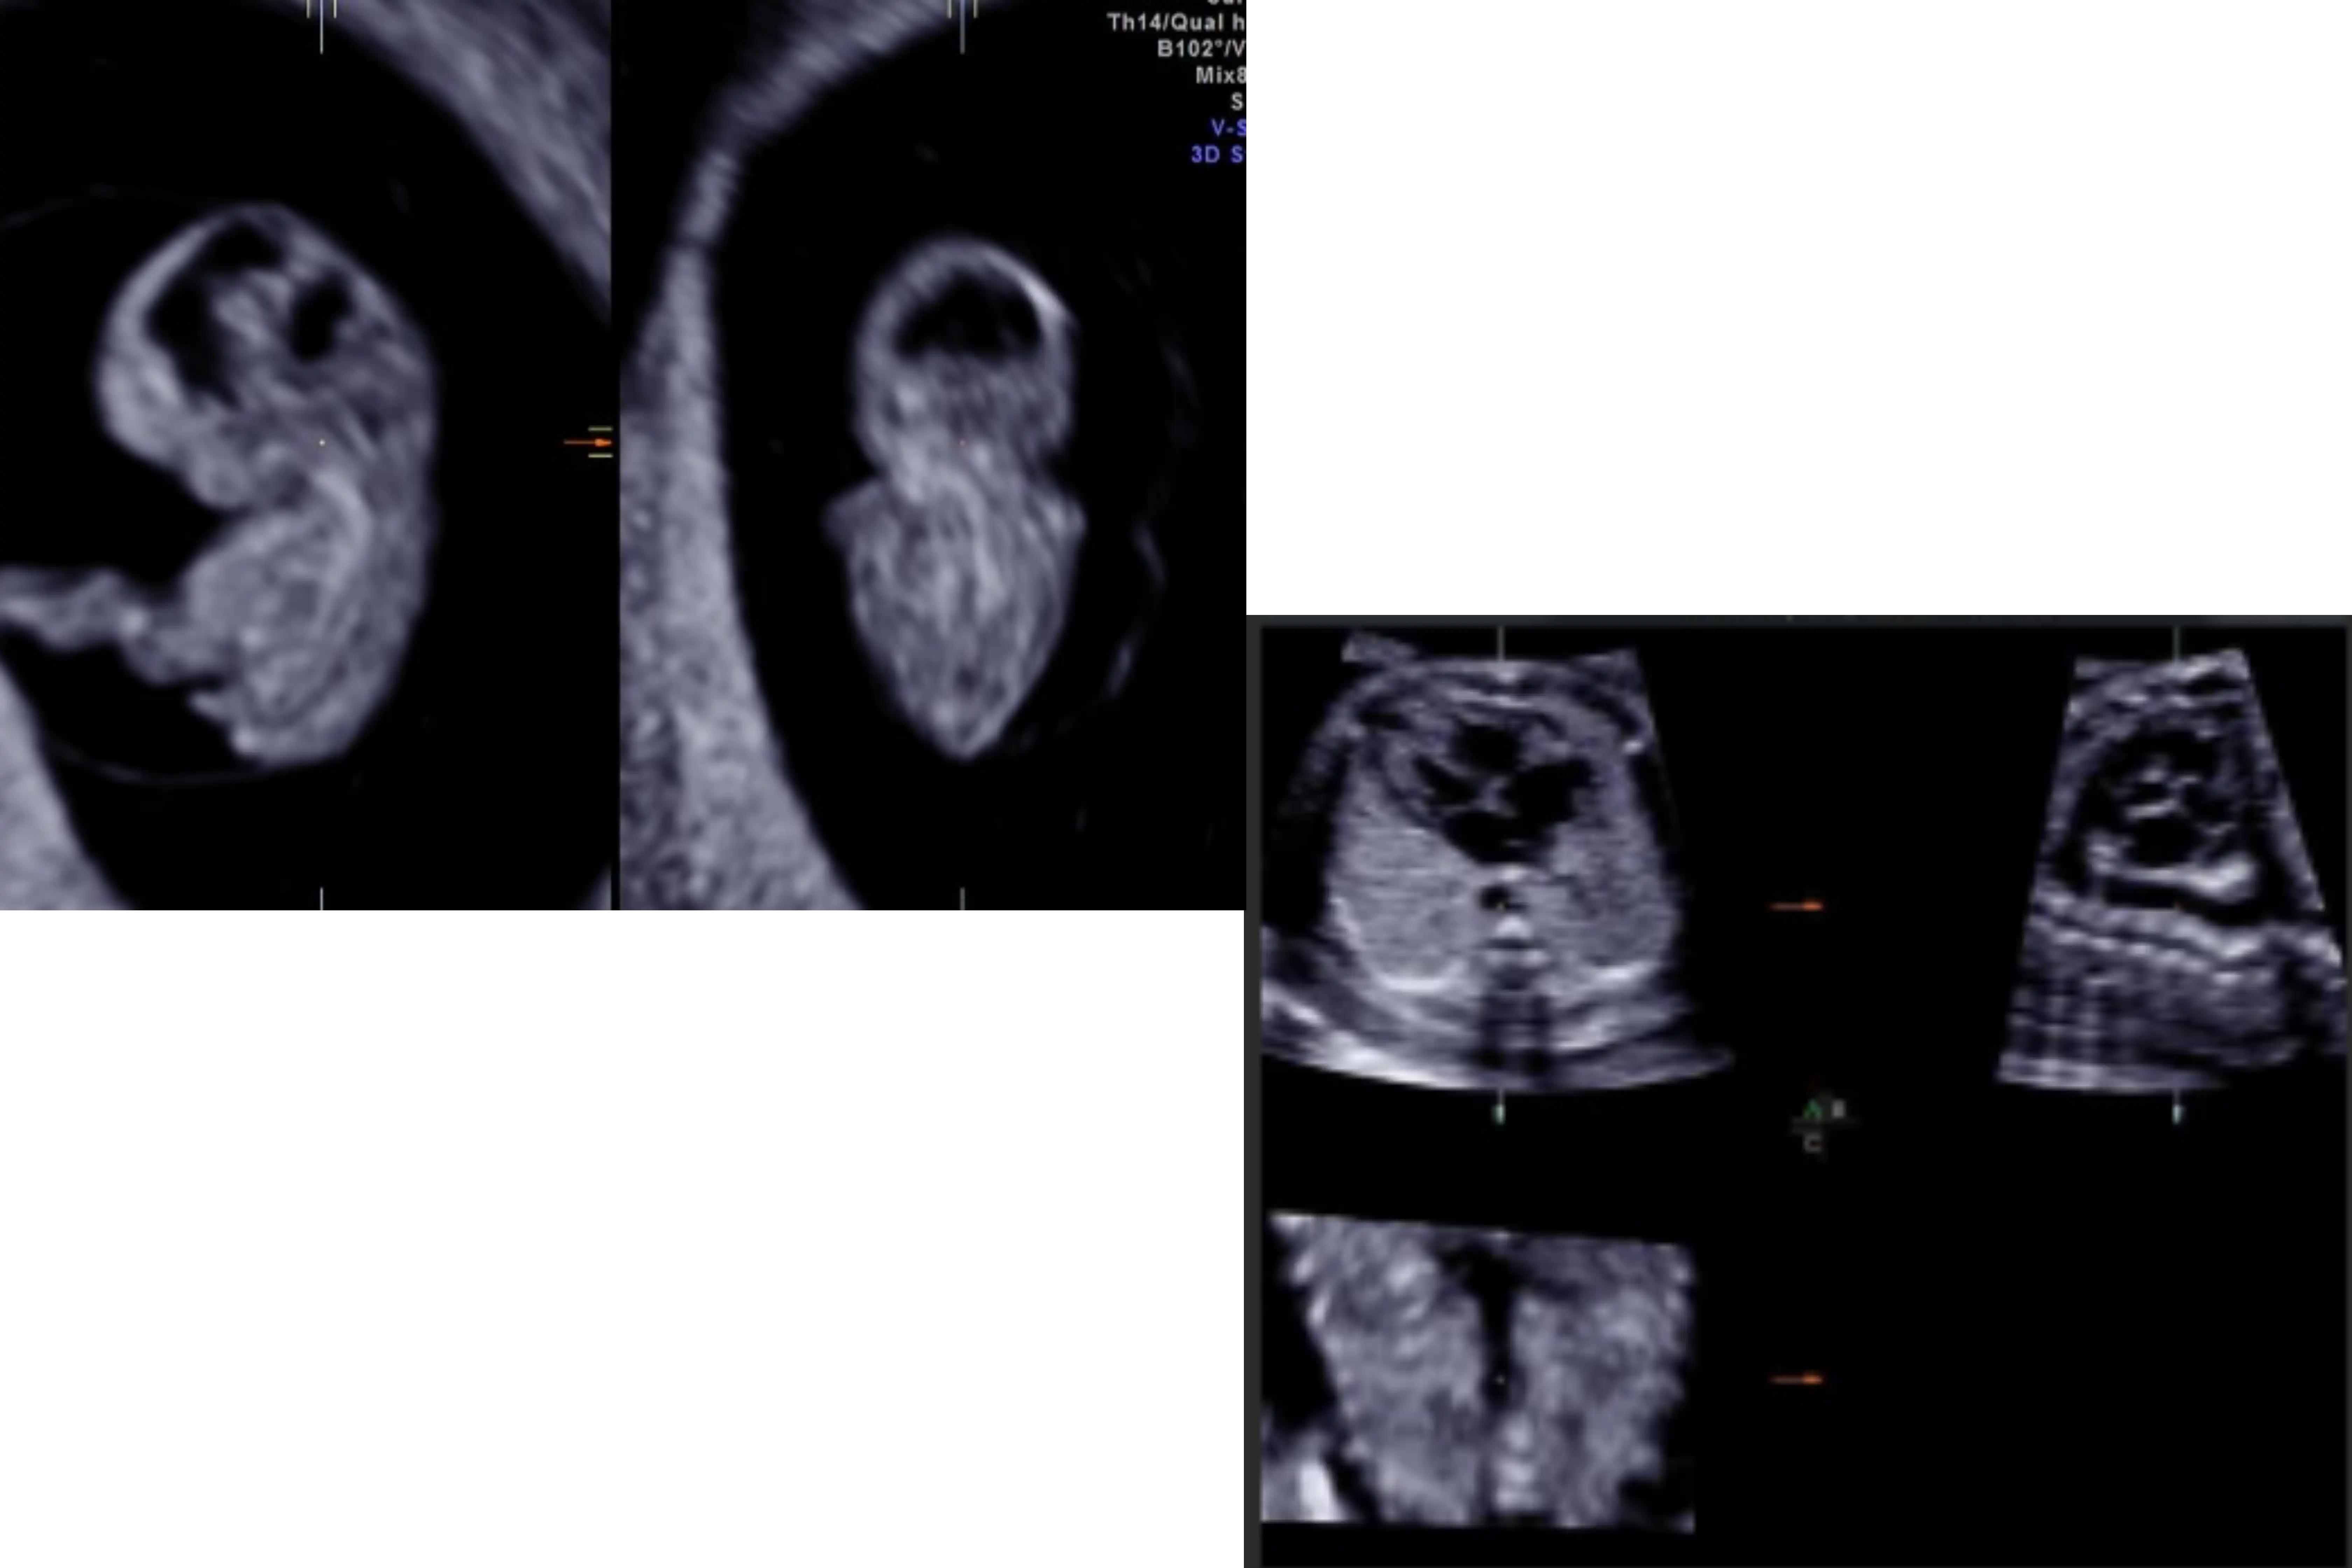

1c. Advanced 3D/4D workshop

Skeletal System

Fetal Brain